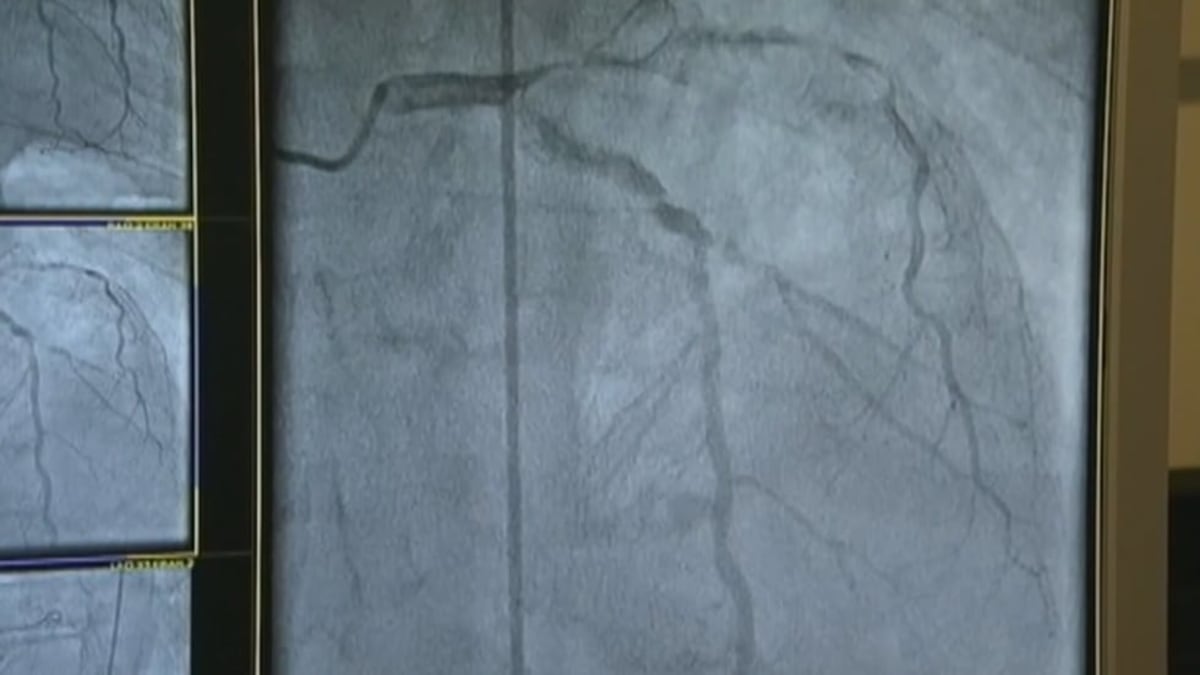

Jordan Lancaster founded Avery Therapeutics through the program to advance tissue-engineered treatments for cardiovascular disease. His company is already in clinical trials with therapies that could treat heart failure in ways currently impossible.